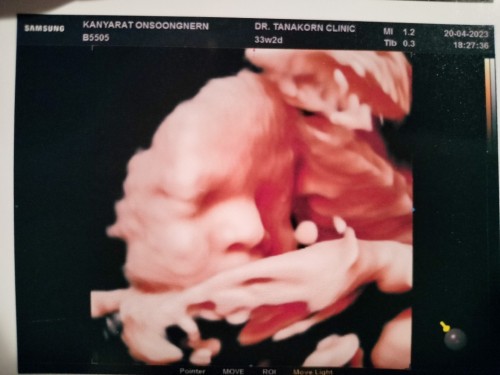

สวัสดี 8 เดือนแล้ว 👶 น้ำหนักเท่าไหร่กันแล้วครับ 33w2d ผมหนัก 2,330g แล้วครับแต่น้ำหนักแม่ผมไม่ขึ้นเลย

🥰ขอบคุณครับ ขอให้ออกมาเป็นเหมือนในภาพซาวด์ 😂😂